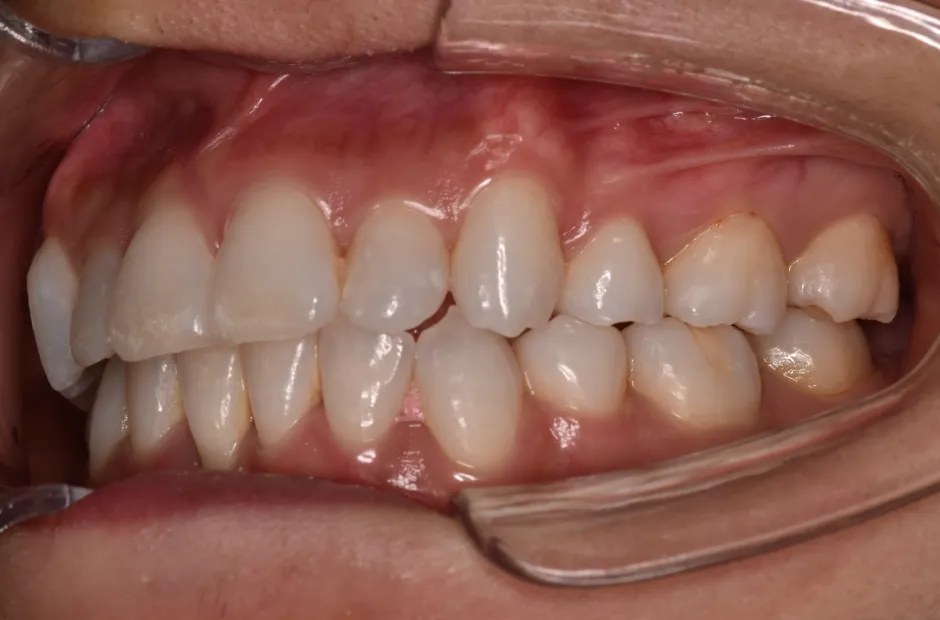

叢生

| 診断名・主訴 | 叢生 |

|---|---|

| 年齢・性別 | 43歳・女性 |

| 治療期間・回数 | 2年7か月 27回 |

| 治療に用いた主な装置 | 舌側矯正 |

| 抜歯部位 | 両顎4,4 |

| 治療費 | 100万円(税抜) |

| リスク・副作用 | 装置による違和感・疼痛・歯肉退縮・歯根吸収・虫歯のリスクなど |

治療前

治療後